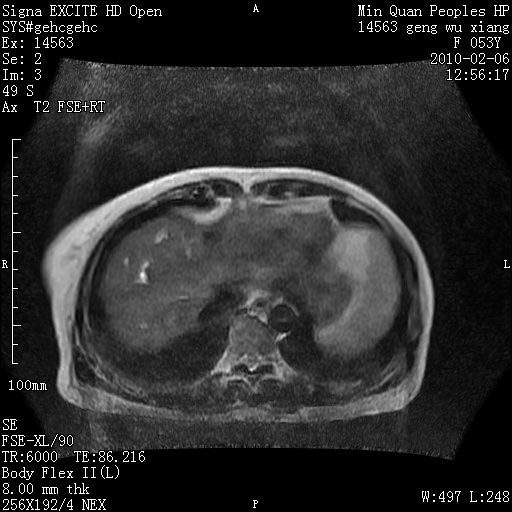

标题: MRI2762:胆道梗阻原因?

f,53y,全身黄染多日。

高位胆道梗阻 胆管癌可能性大

支持 高位胆道梗阻 胆管癌可能性大。